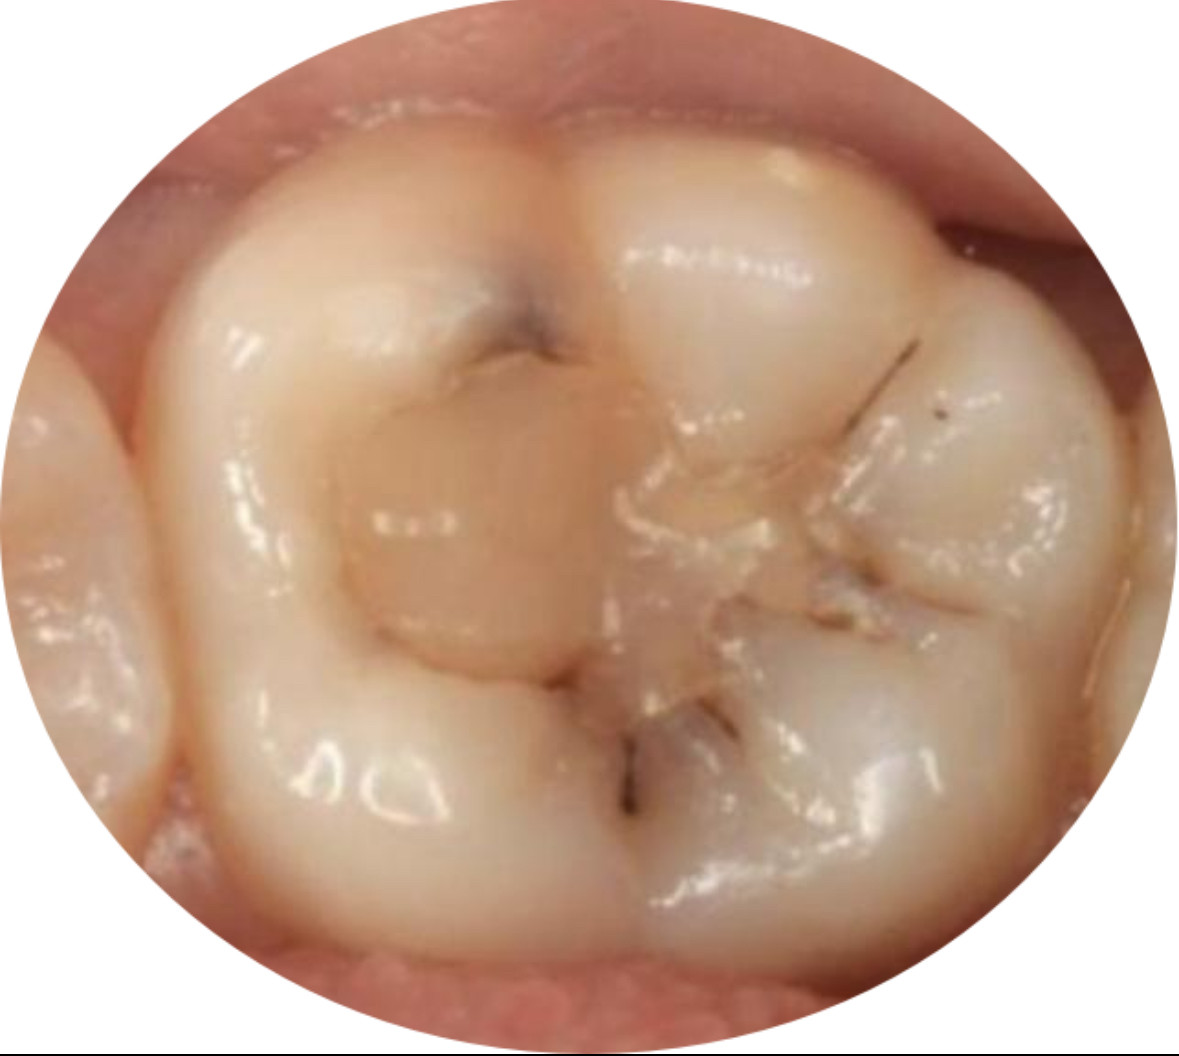

乳牙龋齿是儿童常见的口腔问题,而在乳牙已经补过的情况下,有时仍可能出现新的龋齿,这就是乳牙继发龋。继发龋指的是在乳牙已有充填(补牙)或治疗后的牙齿表面,因牙齿边缘密合不良、口腔细菌侵蚀或口腔卫生不佳,再次出现龋坏的现象。

乳牙继发龋多发生在补牙材料与牙体的接触边缘,这些边缘如果存在微小缝隙,容易成为细菌滋生的温床。一旦继发龋发生,如果不及时处理,可能导致牙齿疼痛、感染,甚至影响恒牙萌出和牙列排列。